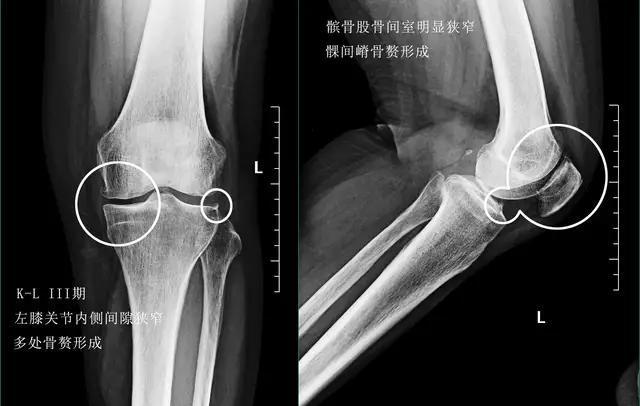

- 诊断:此时通过膝关节x线可以帮助患者进行诊断,在x线上我们可以看到明显的骨质形成,可以看到膝关节间隙的狭窄,这往往是由于软骨磨损,软骨变薄导致的。此时可以通过口服氨糖关节内注射玻璃酸钠或者是富血小板血浆因子,也就是prp来帮助患者控制症状。

- 诊断:后膝关节x线检查就可以明确诊断,我们可以看到关节会有大量的骨赘形成,而且有一些骨赘会影响患者的屈伸幅度,关节间隙会有进一步的狭窄,而且有些患者会因为活动减少出现严重的骨质疏松。